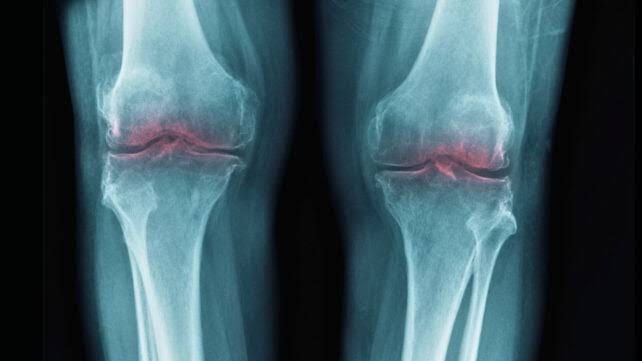

Breakthrough to Restore Aging Joints Could Help Treat Osteoarthritis

A study in mice traced the loss of cartilage that accompanies aging to a single protein, pointing to...

A study in mice traced the loss of cartilage that accompanies aging to a single protein, pointing to treatments that may one day restore mobility and ease...